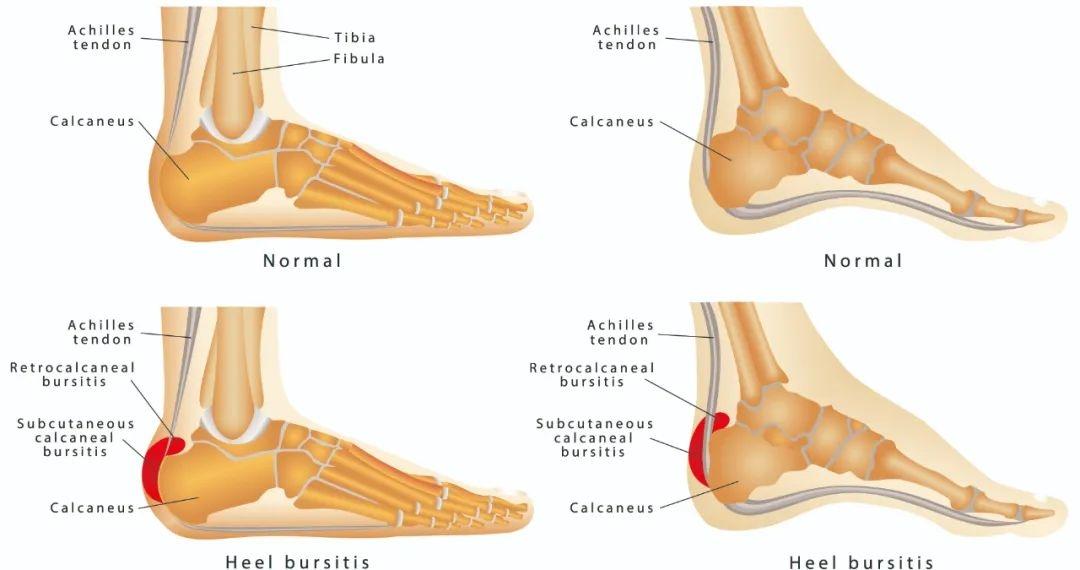

3、 跟骨滑囊炎

足跟部有三个滑囊,皮肤与跟腱之间的称为跟腱后滑囊。跟腱与跟骨后上角之间称跟骨后滑囊。位于跟骨结节下方,称跟下滑囊。

滑囊炎与直接压迫、摩擦有关。站立行走、运动量大是造成跟下滑囊炎直接原因,而所穿鞋后帮过硬、过紧、活动量多是造成跟后滑囊炎的直接原因。

早期在足跟的后上方可见一个小的轻度变硬有压痛的红斑,随着炎症扩散,跟腱可出现一个疼痛的红色肿块,红肿热痛症状明显。